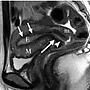

陰道並不是直的,

入口處傾斜角度較緩,靠子宮頸側向背傾斜角度較大,

略呈S形。